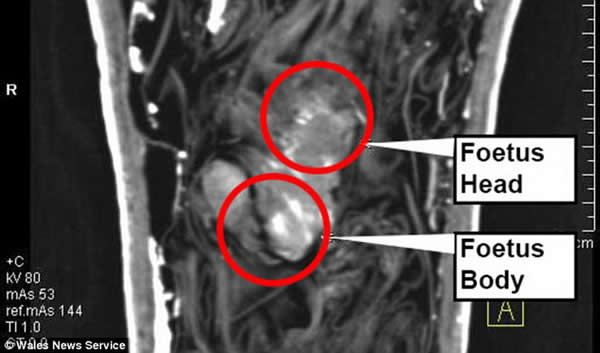

(蜘蛛网报道)据腾讯科学(悠悠):令科学家迷惑40年之久的木乃伊谜团现已揭晓,之前他们曾认为1971年发现的一具小型木乃伊可能是伪造的。但最新CT扫描结果显示,木乃伊中除了多层包裹的亚麻布之外,还有一个10厘米长的胎儿,甚至残留着胎盘液囊,这具木乃伊胎儿可能仅发育12-16周。

这具木乃伊(左图)珍藏在美国斯望西大学埃及研究中心,考古学家分析称其历史可追溯至第26王朝,大约公元前600年。木乃伊涂有黄蓝色假发,较宽的颈圈,红色面孔,这表明是一具男性木乃伊。右图是CT扫描结果,显示木乃伊内部存放着一个婴儿尸体。